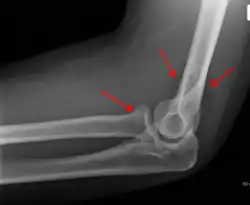

A subtle radial head fracture with associated positive sail sign

• Proximal radius fracture. A fracture within the capsule of the elbow joint results in the fat pad sign or "sail sign" which is a displacement of the fat pad at the elbow.